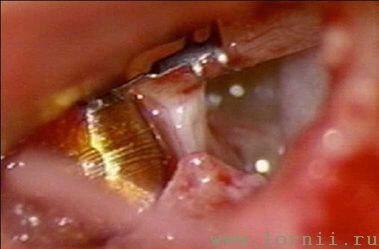

Борами выполнялась антромастоидотомия (рис. 7). Через заднюю тимпанотомию вскрывалась барабанная полость (должно быть хорошо обозримо наковально - стременное сочленение, длинный отросток наковальни и окно улитки), размеры отверстия тимпаностомы должны быть не менее 3-4 мм, для нормального прохождения катушки импланта (рис. 8).

При классической методике (у пациентов с сенсоневральной тугоухостью) катушка импланта фиксировалась на длинной ножке наковальни (рис. 11, 12).